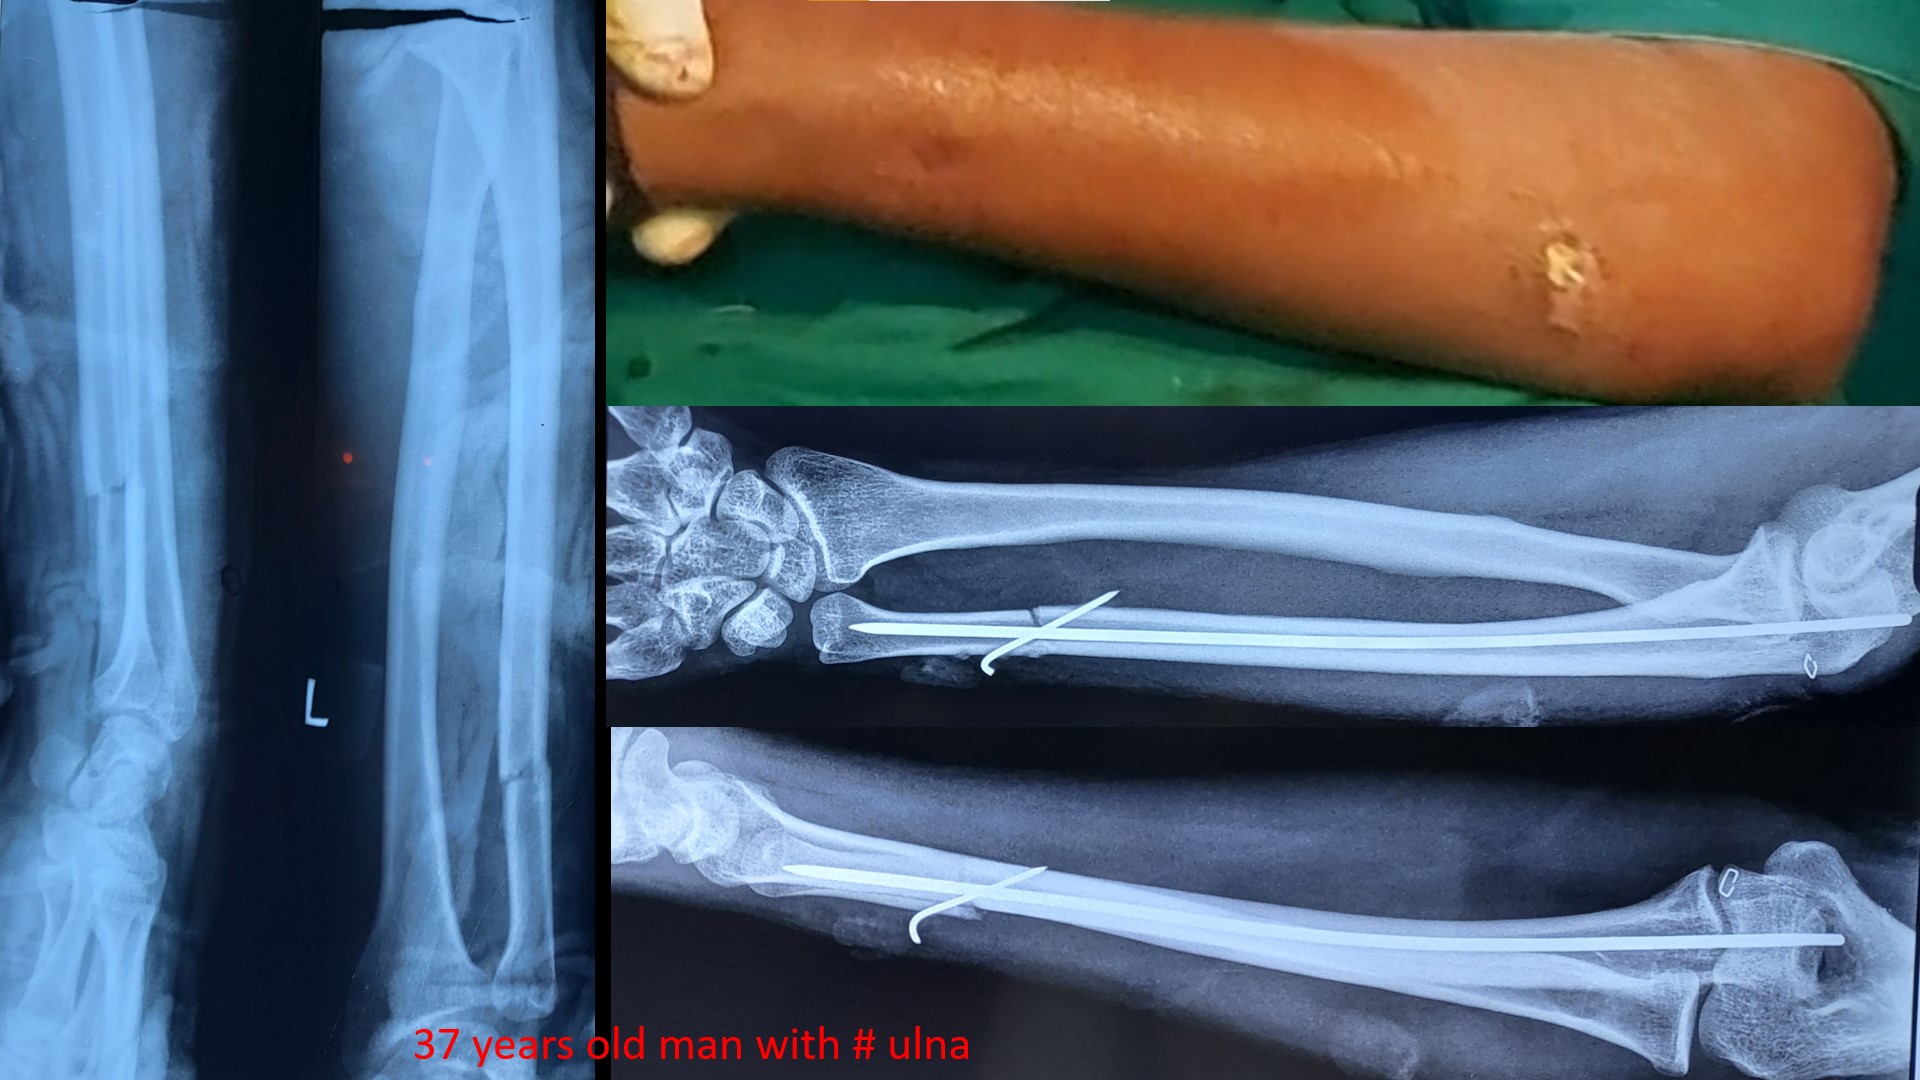

FOREARM FRACTURES